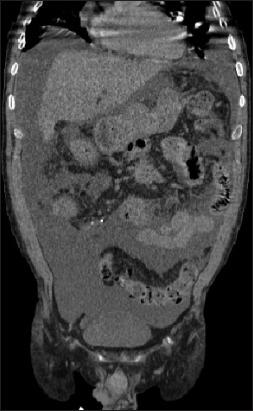

Pancreatic ascites is a rare condition characterized by the accumulation of high-amylase ascitic fluid in the peritoneal cavity. This condition is often associated with chronic pancreatitis, pancreatic trauma, or pseudocyst rupture. Because of its rarity and ill-defined clinical presentation, pancreatic ascites is often a diagnostic and therapeutic challenge in clinical practice. The current diagnostic criteria include an amylase level >1000 mg/dL, a protein level >3 g/dL, and a serum ascites albumin gradient <1.1 g/dL. The clinical features vary, but may include progressive abdominal distension, diffuse abdominal pain, weight loss and peritonitis. The management of pancreatic ascites remains controversial, and there is no consensus regarding the optimal approach. Conservative medical management, which includes nutritional support, pain control, therapeutic paracentesis and the use of somatostatin analogs, has been associated with a high failure rate and significant morbidity. Interventional therapies, such as surgery and endoscopic transpapillary stenting, have shown more promising outcomes. However, the choice between these methods is still debated, with some advocating for endoscopic approaches, because of their minimally invasive nature and reduced morbidity compared with surgical options. Endoscopic approaches remain underutilized in practice, probably because of the need for repeated interventions, the potential risks associated with endoscopic retrograde cholangiopancreatography, or a lack of skilled personnel. Although they show significant perioperative morbidity and mortality, surgical options provide definitive resolution of pancreatic ascites. Herein, we provide an updated review of pancreatic ascites, highlighting advances in diagnostic techniques and therapeutic approaches, and summarizing insights from recent clinical cases and retrospective studies.

胰源性腹水是一种罕见病症,其特征为腹腔内积聚高淀粉酶含量的腹水。这种病症常与慢性胰腺炎、胰腺创伤或假性囊肿破裂相关。由于其罕见性及临床表现不明确,胰源性腹水在临床实践中往往是诊断和治疗上的一大挑战。目前的诊断标准包括淀粉酶水平>1000毫克/分升、蛋白质水平>3克/分升以及血清腹水白蛋白梯度<1.1克/分升。临床特征各异,但可能包括进行性腹胀、弥漫性腹痛、体重减轻和腹膜炎。胰源性腹水的管理仍存在争议,对于最佳治疗方法尚无共识。保守药物治疗,包括营养支持、疼痛控制、治疗性腹腔穿刺放液及使用生长抑素类似物,其失败率较高且发病率显著。介入治疗,如手术和内镜下经乳头支架置入术,已显示出更有前景的结果。然而,这些方法之间的选择仍存在争议,一些人主张采用内镜方法,因为其微创性质以及与手术选择相比发病率较低。内镜方法在实践中的应用仍然不足,可能是因为需要重复干预、与内镜逆行胰胆管造影相关的潜在风险,或缺乏技术熟练的人员。尽管手术选择显示出显著的围手术期发病率和死亡率,但能为胰源性腹水提供确定性的解决方案。在此,我们提供胰源性腹水的最新综述,强调诊断技术和治疗方法的进展,并总结近期临床病例和回顾性研究的见解。